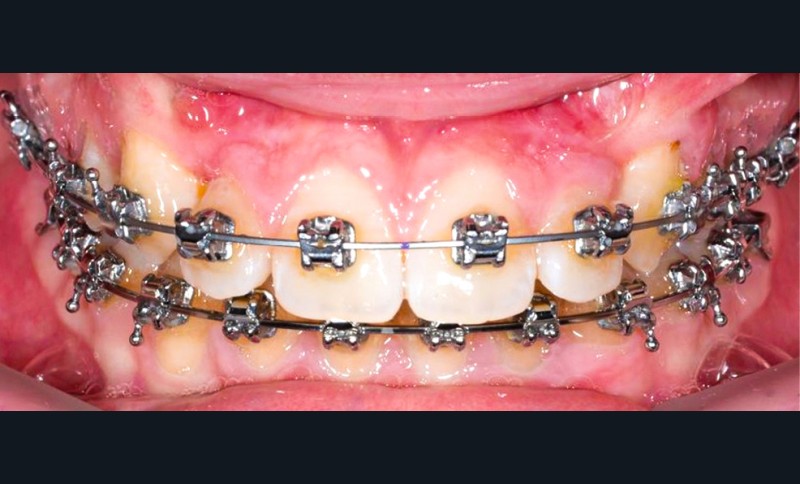

Un appareil multi-attache est mis en place avec une prescription MBT en .022 x .028. une fois les faces vestibulaires des canines maxillaires apparentes. 13 et 23 ne sont pas prises en charge dans l’arc pour éviter les effets parasites sur les dents adjacentes. Leur traction est poursuivie avec des élastiques de Classe II (1/4” – 3.5 oz) en port nocturne. Ces élastiques sont portés sur un bouton palatin pour la 23 afin de corriger sa rotation mésio-vestibulaire. Une fois les canines suffisamment proches du plan occlusal, elles sont prises en charge dans un arc continu en suivant les séquences suivantes : .014, .018 et .019 x .025 Niti. Une fois l’arc .019 x .025 en Niti en place pendant huit semaines, l’arc transpalatin est déposé. L’arcade mandibulaire suit cette même séquence d’arcs avec l’ajout d’un arc en acier .019 x .025 avec courbe de Spee inversée pour aider à la correction de la supraclusion.

À ce stade, une radiographie panoramique est réalisée pour s’assurer de l’intégrité des racines, contrôler les axes dentaires et planifier le repositionnement de certaines attaches ainsi que le collage des tubes sur les secondes molaires en cours d’éruption.

Un arc acier .019 x .025 est inséré à l’arcade maxillaire et les finitions sont réalisées sur des arcs en TMA .017 x .025.